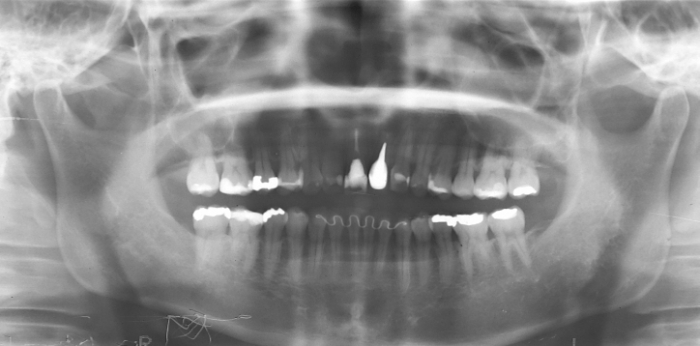

Raio X inicial

Raio X com implante e prótese provisória fixa

Raio X com dente de porcelana instalado